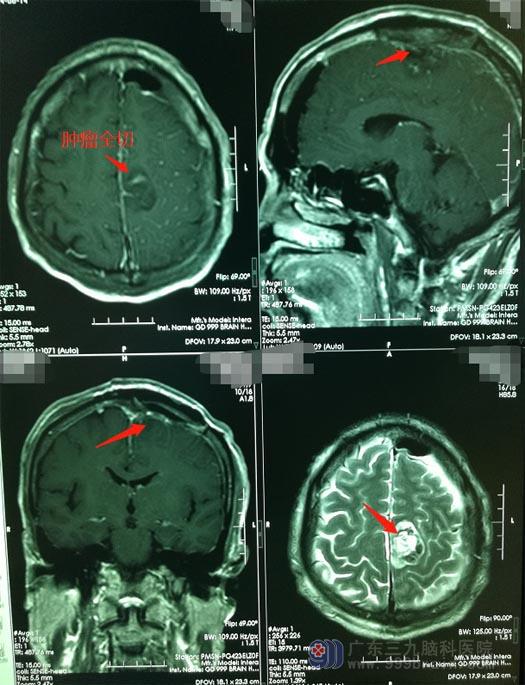

广东三九脑科医院神经外五科主治医师李兴可详细询问和了解吴叔的病情后,及时确定了手术方案。在医院副院长、神经外五科主任鲁明带领下行“左侧额顶部镰窦旁占位性病变切除术”,手术非常顺利。

术后第二天,吴叔手脚活动自如、麻木感消失,可以下床活动。想起三年前的倔强和固执,他自己都有点不意思了。

▲手术后